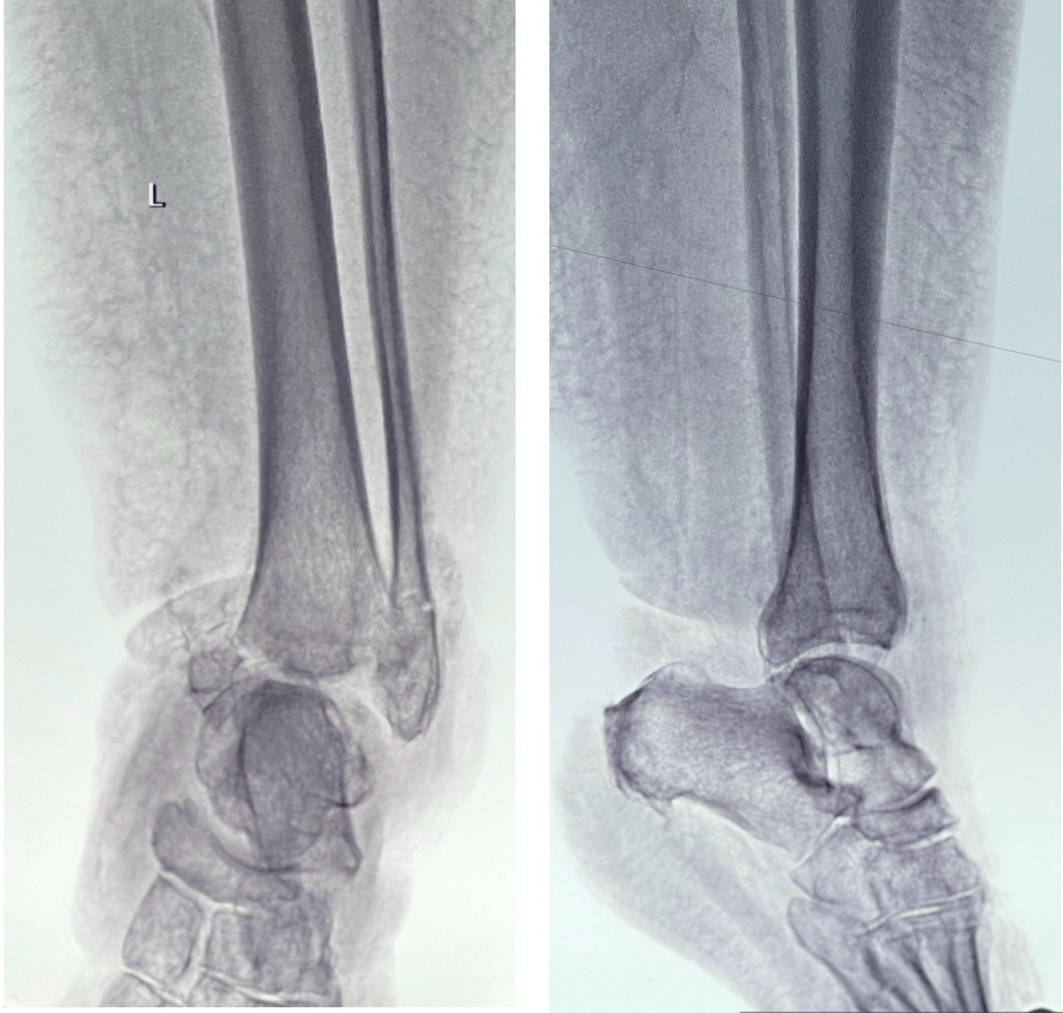

В данном конкретном случае повредилось всё, включая артерию. Я второй раз в жизни вижу такого пациента, в обоих случаях имеет место очень сильно лишний вес. Подозреваю, что именно из-за веса случился вывих, а не более простая травма. Так вот в тот первый раз дело закончилось ампутацией. Этой женщине повезло больше (где-то за Полярным кругом, кстати, респект коллегам!!) - повреждение артерии выявили сразу, сразу же наложили шунт - спасли ногу! При габаритах ноги, подозреваю, было очень непросто. Думаю, что габариты сыграли и еще одну злую шутку - пропустили перелом лодыжек. Это не уникальная ситуация, часто при политравме пропускают, когда человека в тяжелом состоянии привозят, с множественными травмами, и еще нет толком ни отека, ни гематомы, а пожаловаться человек не может, или всё внимание оттягивают более тяжелые повреждения.

Думаю, так и было. Стопа ничего не чувствует, отека не видно. В итоге, когда перелом лодыжек выявили, было поздно. Попытки закрытой репозиции и фиксации спицами успеха не имели. Результат - паралитическая стопа с фиксированной эквинусной установкой стопы. Попросту говоря, вывести стопу под углом 90 градусов стало невозможно. Соответственно, нормально наступать на ногу - тоже. Напомню, что в колене разорваны все связки. И лишний вес никуда не делся. Ходьба - только с костылями, высокий риск падения. Перегрузка других суставов, позвоночника - так себе перспектива.